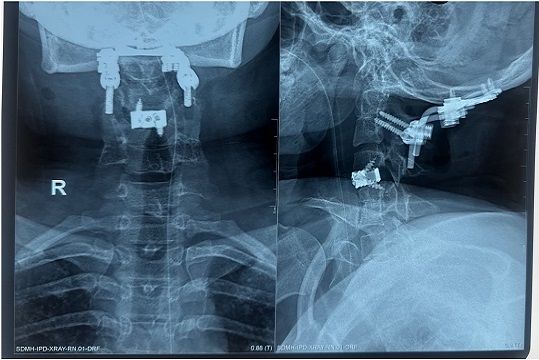

Spinal Surgery

Treatment for spinal cord injuries, degenerative diseases, and deformities.